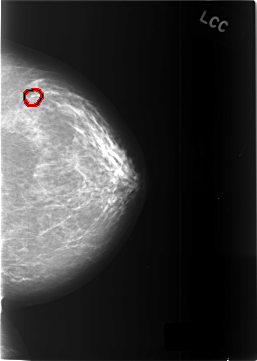

C_0449_1.LEFT_CC

LEFT_CC LINES 5776 PIXELS_PER_LINE 4104 BITS_PER_PIXEL 12 RESOLUTION 50 OVERLAY

FILE: C_0449_1.LEFT_CC.OVERLAY

TOTAL_ABNORMALITIES 1

ABNORMALITY 1

LESION_TYPE CALCIFICATION TYPE DYSTROPHIC DISTRIBUTION CLUSTERED

ASSESSMENT 4

SUBTLETY 5

PATHOLOGY BENIGN_WITHOUT_CALLBACK

TOTAL_OUTLINES 1

BOUNDARY